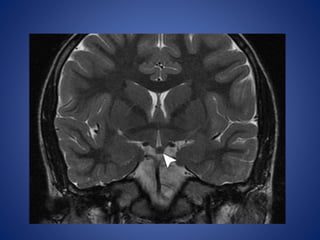

Hypothalamic Hamartoma

Hypothalamic hamartoma is the lesion most commonly associated

with CPP, being implicated in up to 60% of cases.

Hypothalamic hamartomas may be either

• sessile (intrahypothalamic) or

• pedunculated (parahypothalamic).

Imaging Features.—

Sessile hypothalamic hamartomas may expand the hypothalamus.

Pedunculated hypothalamic hamartomas usually arise from the

floor of the hypothalamus and extend inferiorly.

They are typically isointense relative to gray matter with T1- and

T2-weighted sequences, although they may be mildly hyper- or

hypointense relative to gray matter with T2-weighted sequences